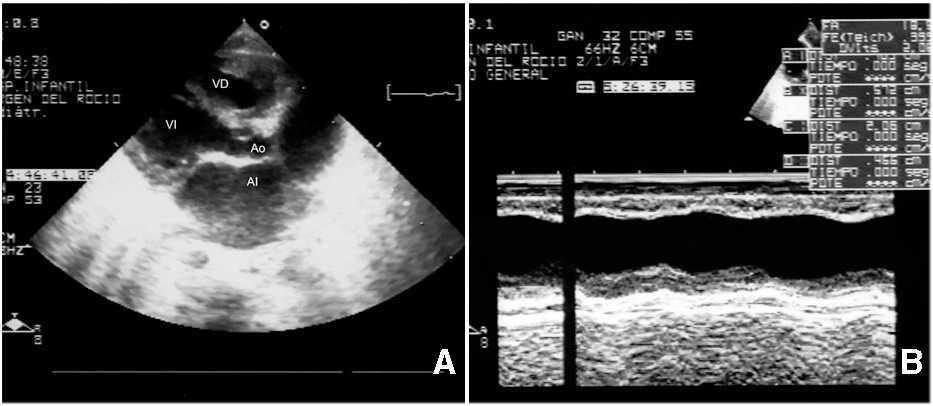

A los 10 días de vida presentó bruscamente disnea por edema pulmonar, cardiomegalia, hipotensión arterial y oliguria. En sus electrocardiogramas (ECG) se apreciaban voltajes muy atenuados de los complejos, y en la ecocardiografía, una gran dilatación de cavidades izquierdas (DdVI: 38 mm) con insuficiencia mitral moderada y gravísima afectación de la contractilidad (fig. 1). El cuadro era compatible con miocarditis aguda grave.

Figura 1. Dilatación de cavidades izquierdas (10 días de vida): A) Ecocardiografía 2D, proyección paraesternal de eje largo: enorme dilatación de la aurícula izquierda: relación AI/Ao 3.B) Ecocardiografía modo M del ventrículo izquierdo (10 días): dilatación del ventrículo izquierdo con importante afectación de su contractilidad; AF: 18,5; FE: 35,5 %.